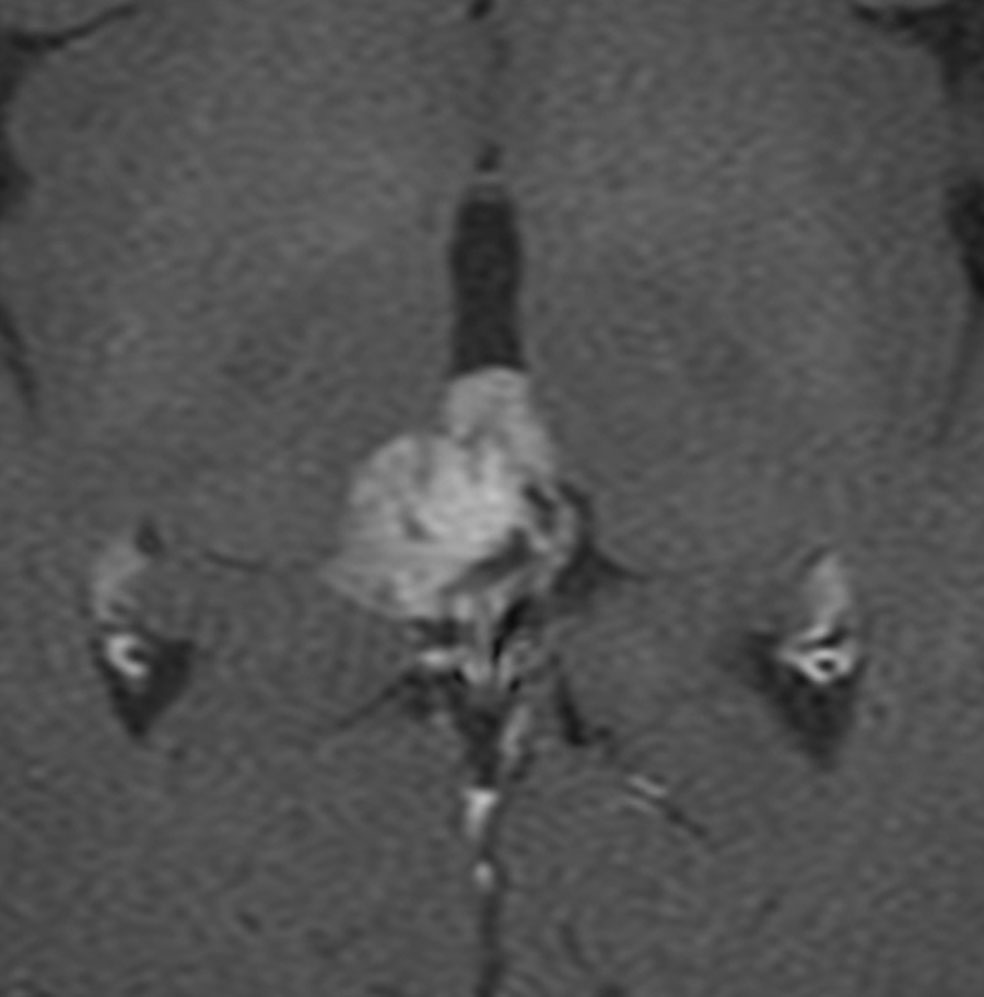

でも腫瘍増大が止められずに,発症1年後に54グレイ30分割の放射線治療を受けています。さらにその半年後くらいから再増大しましたが,スードプログレッションと考えられました。上左MRIは放射線治療前,上右MRIは放射線治療1年後です。毛様細胞性星細胞腫は放射線治療後に一過性増大(多くはのう胞性増大)することが多いです。

のう胞性拡大が止まらず,発症3年後にまた再開頭手術 (left occipital transtentorial approach) で亜全摘出しました。右は術後の画像です。初発時の最初の手術で亜全摘出あるいは全摘出 gross total removalできていればと思える例です。